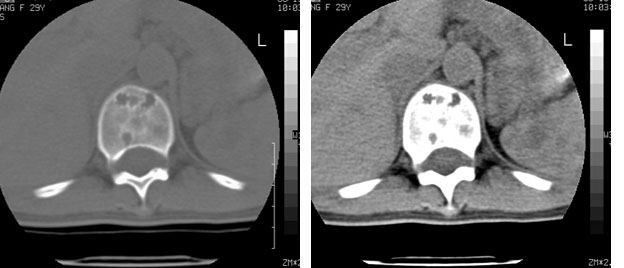

车祸致t12压缩性骨折,行ct扫描意外发现椎体多发肿瘤样病变,建议加拍骨盆平片,患者平常无症状。

症状和影像表现都不符合骨髓瘤表现(多骨普遍骨质疏松,穿凿样骨质破坏周围无硬化)

考虑多发血管瘤

考虑多发骨髓瘤可能性大。(骨松质内弥漫性分布,边缘清晰的溶骨性破坏,无硬化。睥脏增大,其内有多个圆形底密度影。淋巴瘤不除。

1:胸腰椎多发破坏伴骨折,近似穿凿样,考虑骨髓瘤,但有好多不符只出1、发病年龄小、女性,2、病变似有硬化环。2:淋巴瘤可能性大,骨及脾脏均有改变(脾脏改变似与外伤关系不大)建议密切结合临床及相关检验进一步诊断,期待结果。

椎体多发性溶骨性破坏,部分融合,椎旁无软组织肿块、椎间隙正常,t12 压缩,脾脏增大,其内示多发低密度影,首先考虑多发性骨髓瘤。病人较年轻,平素无异常,转移瘤可能性小。